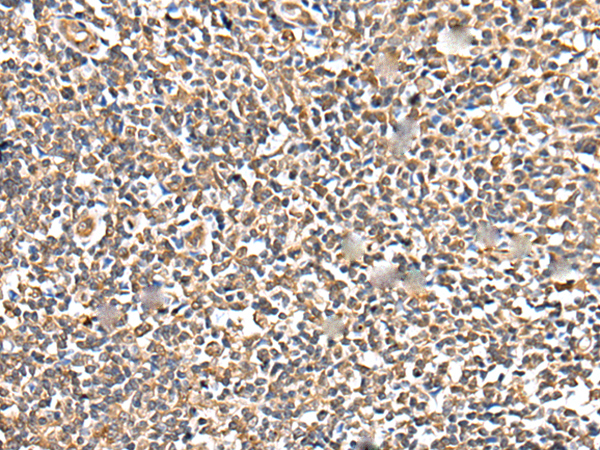

分类: 科研抗体货号: P02115别名: BCL7应用: IHC反应种属: Human, Mouse